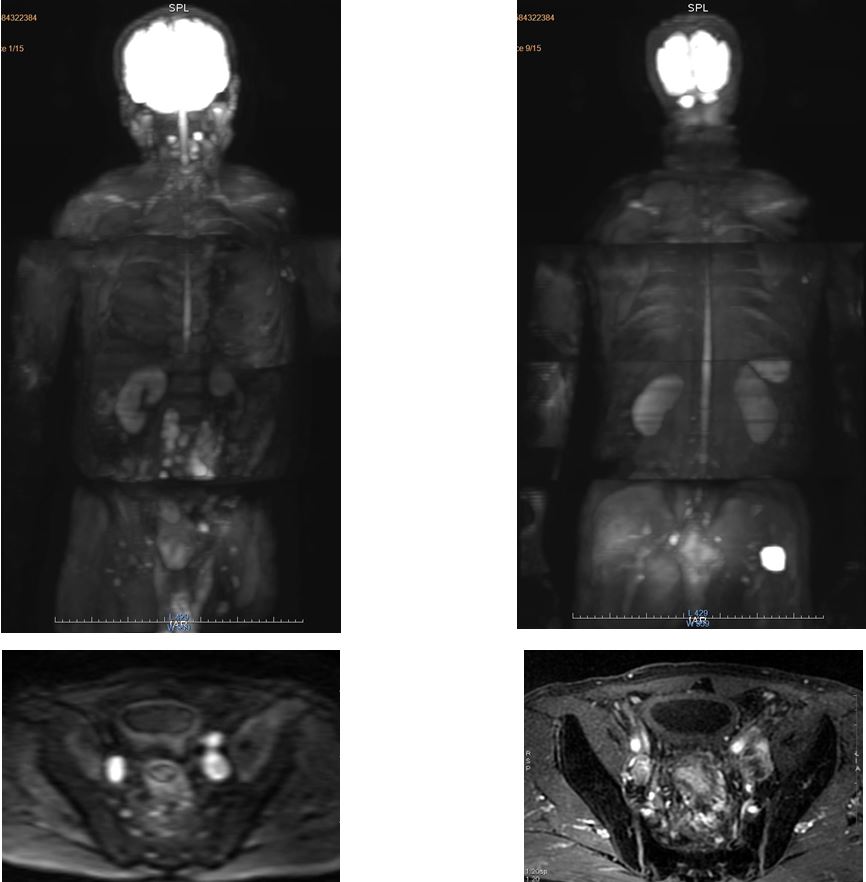

Phát hiện Hubet8000.com Casino & Thể Thao Link Mới trực tràng di căn hạch trên cộng hưởng từ toàn thân

Tóm lại, chụp cộng hưởng từ toàn thân cho một khảo sát rộng gần toàn bộ cơ thể nên có đánh giá tổng quát sàng lọc các tổn thương trong cơ thể, đặc biệt trong việc tầm soát Hubet8000.com Casino & Thể Thao Link Mới, Hubet8000.com Casino & Thể Thao Link Mới di căn và theo dõi sau Hubet6677 phiên bản mới.